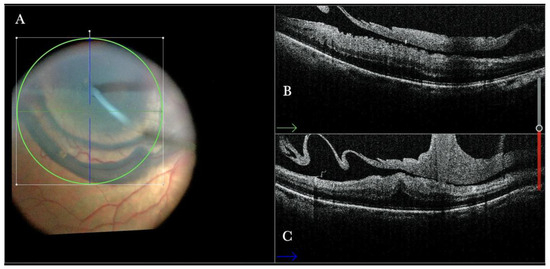

Figure 20.

(A) Microscope view of the same case of retinal detachment with proliferative vitreoretinopathy (PVR). The retinotomy is analyzed. The surgeon needed to decide whether to peel the epiretinal membrane (ERM) at the edge of the retinotomy and elevate the retinotomy to lower the traction. It is not clear through the microscope how to proceed. (The green box indicates the field-of-view of the OCT scan, the green and blue lines within the green box show the vertical and horizontal scan planes). (B) The horizontal (green arrow) intraoperative optical coherence tomography (i-OCT) scan shows the retinotomy, indicating the presence of an ERM and squared edges. (C) The vertical (blue arrow) i-OCT scan shows the same area after peeling the ERM, elevating, and reattaching the retinotomy. The retinotomy is now flat and relaxed.